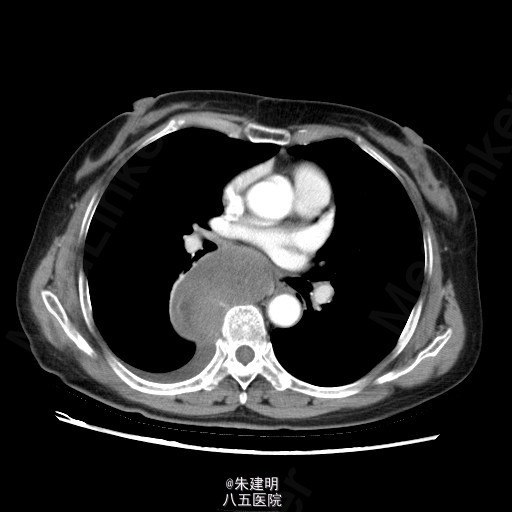

【主诉】 胸部不适1月 【现病史】 患者1月前于当地医院常规体检发现纵隔部占位,为明确诊断,遂来我院门诊就诊。门诊行CT检查(2015-05-07)示:右后下纵膈占位,梭形细胞肿瘤(神经源性等)机会大,右侧少量胸腔积液;左肺炎性小结节机会大,随访。门诊拟诊断为“右侧纵隔占位”收入我科。患者病程中,一般情况可,胃纳二便无殊。

查体: T:36.6℃ P:78次/分 R:20次/分 BP:120/80mmHg 神清,一般可,双侧锁骨上淋巴结未及肿大;胸廓无畸形,呼吸运动平稳,胸廓活动度可;两肺呼吸音清,未及明显干湿罗音。 辅助检查: 门诊行CT检查(2015-05-07)示:右后下纵膈占位,梭形细胞肿瘤(神经源性等)机会大,右侧少量胸腔积液;左肺炎性小结节机会大,随访。